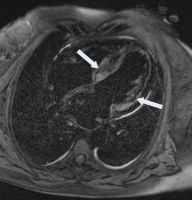

MRT

Abbildung 1: MR des Herzens, 4-Kammer-Blick: LGE-Anreicherung im Bereich des Septums und LV (Pfeil)